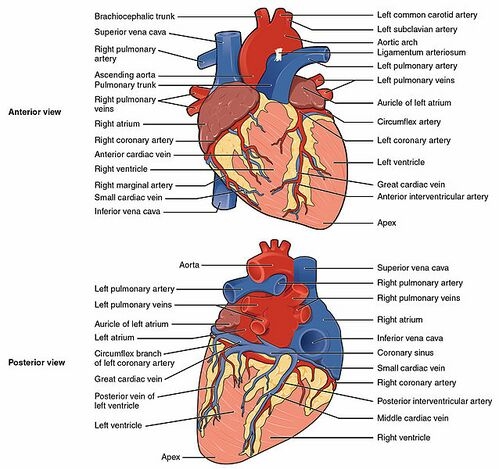

Effect of Chronic Sleep Deprivation on the Histological Architecture of the Heart of Rats With Peptic Ulcer'